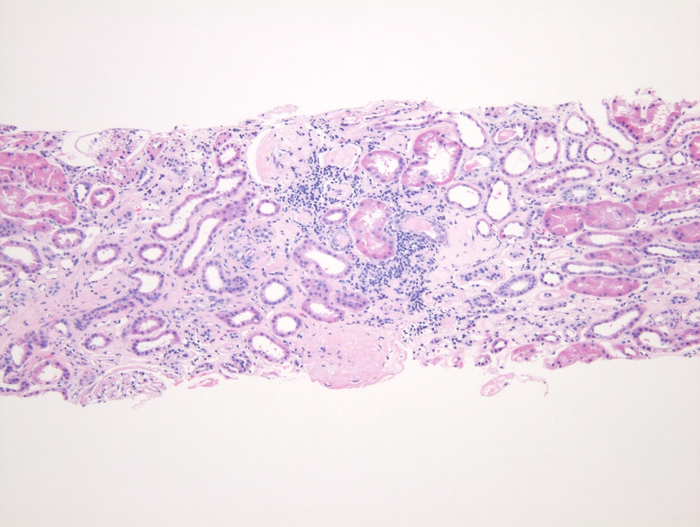

图片:病变肾脏的活检图像,显示管状结构的疤痕和损伤

图片来源:Ashish Verma博士